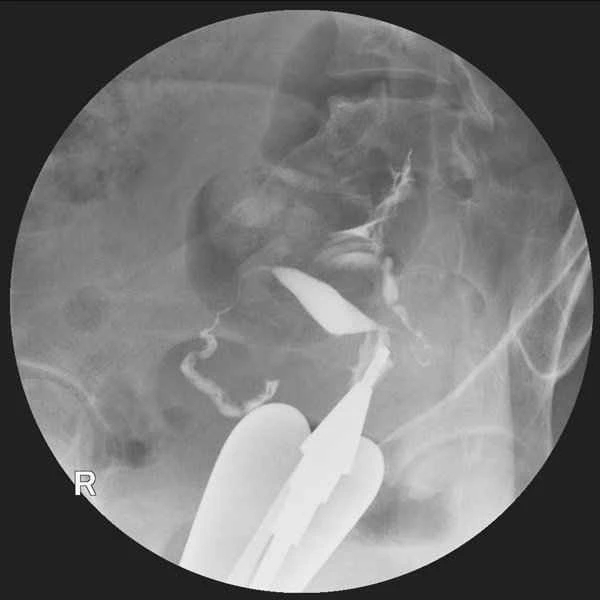

Small bowel obstruction can lead to intestinal decompression. When the small intestine is obstructed, gas and fluid cannot pass through normally, causing them to accumulate. This accumulation increases intestinal pressure. To relieve this pressure, an intestinal decompression tube is sometimes used to drain the accumulated gas and fluid, thereby reducing intestinal pressure, improving blood circulation, and preventing intestinal necrosis.

Intestinal decompression is a common treatment used to relieve pressure caused by intestinal obstruction. Its mechanism of action involves inserting a thin catheter into the intestine to drain accumulated gas and fluid, thereby reducing pressure within the intestine. This process not only helps relieve the patient's symptoms but also prepares the ground for subsequent treatment, such as determining whether surgical intervention is necessary. Intestinal decompression is typically performed in conjunction with imaging studies and other clinical evaluations to determine the optimal treatment plan.

While intestinal decompression is an effective treatment for small bowel obstruction, it also carries certain risks. For example, improper operation may lead to complications such as infection or perforation. Intestinal decompression does not resolve the underlying obstruction; it only provides temporary symptom relief. Simultaneously with intestinal decompression, doctors need to identify the cause of the obstruction and develop an appropriate treatment plan. This requires a comprehensive consideration of the patient's specific circumstances, including the type, location, and severity of the obstruction, as well as the patient's overall health.